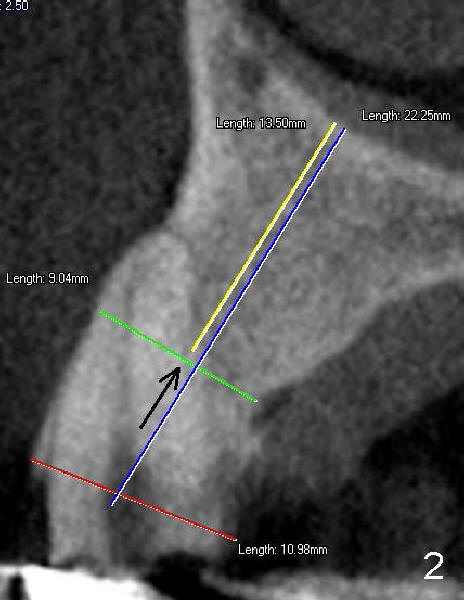

A 73-year-old man feels that upper right bridge is loose. There is subgingival caries (*) under one of its retainers (#6 in Fig.1). CBCT shows that bone volume is sufficient for immediate implant at #6 (Fig.2). When the bridge is sectioned between the pontic #7 and retainer #8, the pontic #7 and retainer #6 complex falls out by themselves. The tooth #6 is deemed nonsalvageable (albeit vital); the labial plate of #7 is atrophic (Fig.3).

Immediately after atraumatic extraction of #6 residual root, the socket is irrigated with normal saline and Chlorhexidine. There is no granulation tissue in the apical area. The root stump is 6 mm mesiodistally and 8.5 mm labiopalatally. Tatum 2 mm pilot drill is used with copious irrigation to penetrate the palatal plate of the socket (as shown by arrow in Fig.2) at the depth of 20 mm from gingival margin. Bicon reamers (cylindrical, from 2.5 mm to 4.0 mm in a sequential order) are used (with 400:1 reduction) for osteotomy without irrigation. Autogenous bone graft is collected to fill the gap between implant and socket. Fig.4 shows 3.0 mm reamer in place (20 mm from the gingival margin). Finally Tatum tapered implant 6x20 mm is torqued in with primary stability (Fig.5: I). There is no gap between the implant and the socket except palatally, where the bone graft is inserted. Two release incisions are placed palatally. The flap is raised. The periosteum is scored at the base. The palatal flap is advanced labially to close the palatal gap with 4-0 chromic gut suture.